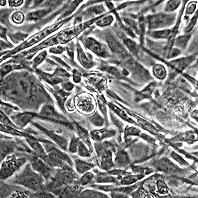

Морфология: веретеноподобная, встречаются большие многоядерные клетки.

Способ культивирования: монослойный